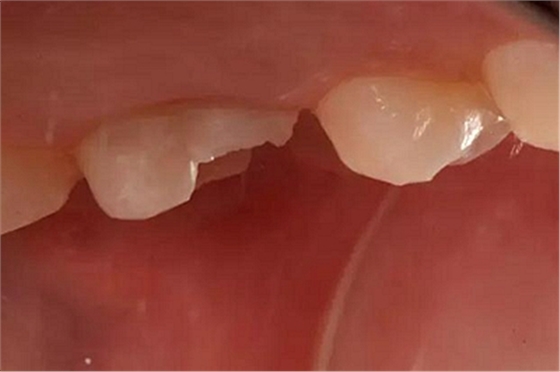

患者女性,55歲,3年前B3纖維樁+鑄瓷全冠修復(fù),一周前牙冠折斷,就診后,發(fā)現(xiàn)纖維樁根管口處折斷,周圍牙齦增生,建議患者行冠延長手術(shù)。首先去除斷端的纖維樁。拍片示牙根長度充足。于是開始冠延長手術(shù)。

因為是前牙,故該患者將來修復(fù)體邊緣必須為齦下,所以3個月后再行修復(fù)。以下為手術(shù)前照片。

以下為術(shù)中照片。

內(nèi)斜切口,頸圈組織,改良垂直褥式縫合。